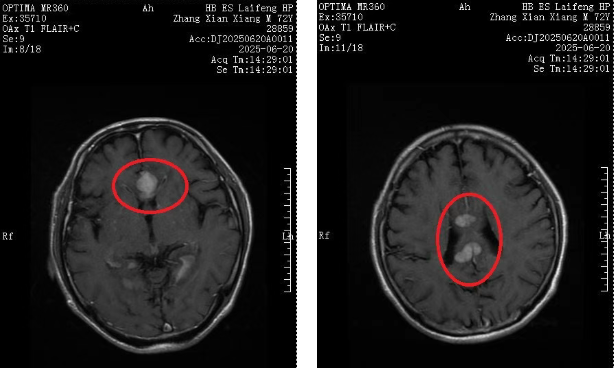

可谁也没料到,今年6月,化疗结束仅两个月,张大爷突然频繁头晕头痛、行走不稳,需要借助拐杖才能勉强活动。家人急忙再次送他到我院就诊,头颅核磁共振结果出来的那一刻,所有人的心又沉了下去:颅内多发转移,病情出现恶化!

就在全家陷入绝望之际,正在我院对口帮扶的湖北省肿瘤医院专家黄青教授详细翻看了张大爷既往接近100多页的病历,反复对比历次影像资料,同时通过远程会诊的方式与另外两名帮扶专家张曲和张平平教授交换治疗意见。最终,结合张大爷的身体状况,黄教授为他制定了新的 “靶向药物+化学治疗” 的个性化方案,还特意叮嘱肿瘤科医护团队:“老人年纪大,要多关注他的情绪变化和药物不良反应!”

经过3个周期的治疗,终于,最近一次复查显示,张大爷颅内的转移病灶基本消失,头晕、行走不稳的症状也完全缓解,已经完全脱离了拐杖,活动自如,连家属都称赞道: “这是超出预期的好疗效!”出院当天,张大爷与其家属特地送来锦旗表示感谢。